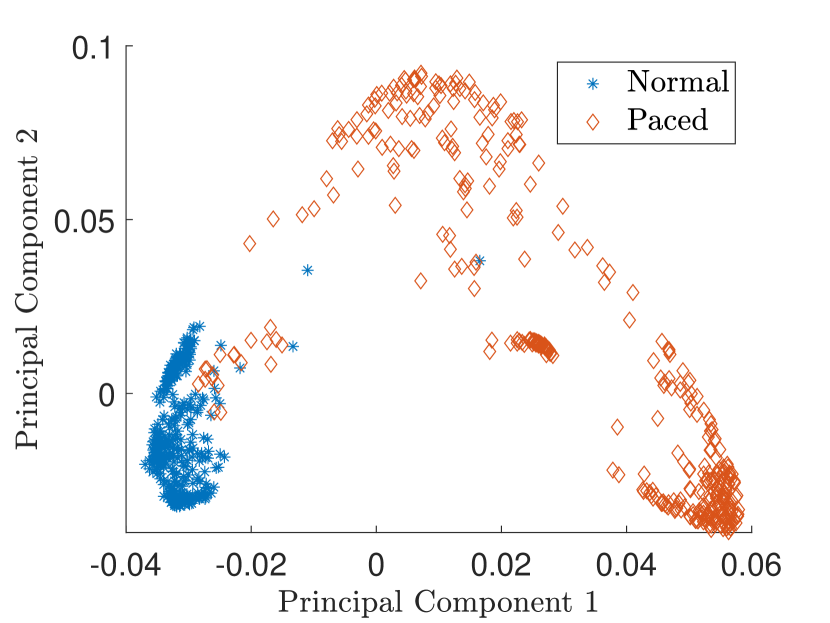

Besides the previous examples of latent space exploration for image datasets, kernel PCA is also applicable to other types of data. In this section, the MIT-BIH Arrhythmia dataset [19] is considered consisting out of ECG signals. The goal is to demonstrate the use of kernel PCA to extract interpretable directions in the latent feature space of the ECG signals.This would allow a clinical expert to gain insight and trust in the features extracted by the model. Similar research was previously done by [7] where they investigated the use of disentangled variational autoencoders to extract interpretable ECG embeddings. A similar approach is used to preprocess the data as in [7].

The signals from the patients with identifiers 101, 106, 103 and 105 are used for the normal beat signals and the data of patients 102, 104, 107, 217 for the paced beat signals. This results in a total of 785 beat patterns which are processed through a peak detection program [20]. The ECG signal is first passed through a fifth-order Butterworth bandpass filter with a lower cutoff frequency of 1Hz and upper cutoff frequency of 60Hz. The ECG beats are sampled at 360Hz and a window of 0.5 seconds is taken around each R-wave resulting in 180 samples per epoch. A regular Gaussian kernel with bandwidth is used, with . The first 10 principal components are used in the reconstruction.

In Fig. 9 the latent feature space projected on the first two principal components is shown. Kernel PCA is also able to separate between the normal and paced beats.

Fig. 10 shows the result in input space of moving along the first principal components in the latent feature space. As original base point we take a normal beat signal, i.e. corresponding to a hidden unit on the bottom right of Fig. 9(a). The smooth transition between the beat patterns allows for interpretation of the first principal components. This allows a clinical expert to understand on what basis the paced beats are separated by the principal components and if this basis has a physiological meaning. In order to investigate the separated region of the latent space at the top of Fig. 9(b) we start from a paced beat pattern and vary along the third principal component. This allows us to see which sort of heartbeat patterns are responsible for this specific distribution in the latent space.